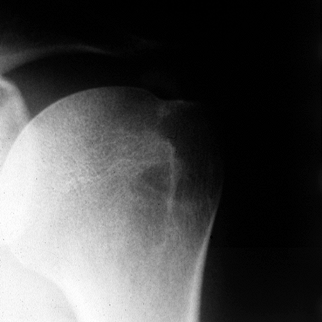

![]() |

Figure 79.3. Anteroposterior radiograph of calcium deposits in a supraspinatus tendon located well medial to its insertion.

dense, well-defined opacities or are fluffy with irregular outlines.

The calcific deposit usually appears within the substance of the

supraspinatus tendon distinct from its bony insertion (Fig. 79.3).